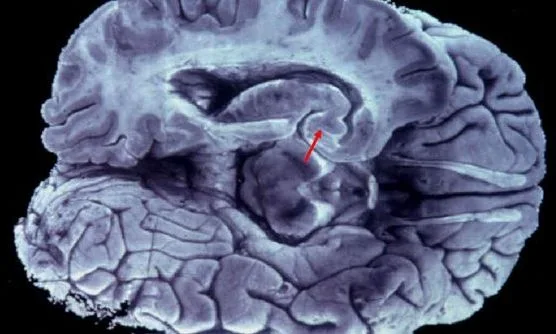

Η μελέτη, που δημοσιεύθηκε στην πλατφόρμα bioRxiv, ξεκίνησε με στόχο την ανάλυση συσσωρεύσεων β-αμυλοειδούς σε ζωικά μοντέλα με παθολογία παρόμοια με τη νόσο Αλτσχάιμερ. Κατά τη διάρκεια των πειραμάτων, ο ερευνητής Shiju Gu παρατήρησε τυχαία σωληνοειδείς σχηματισμούς, οι οποίοι δεν αντιστοιχούσαν σε καμία γνωστή ανατομική δομή. Οι σχηματισμοί αυτοί εντοπίστηκαν σε περιοχές όπως ο φλοιός, ο ιππόκαμπος και ο υποθάλαμος – περιοχές που σχετίζονται με τη μνήμη, τη λογική και τη ρύθμιση βασικών λειτουργιών.

Οι επιστήμονες εκτιμούν ότι οι δομές αυτές περιβάλλουν αιμοφόρα αγγεία και πιθανώς συνδέονται με τα λεμφικά αγγεία των μηνίγγων, γεγονός που υποδηλώνει ότι θα μπορούσαν να αποτελούν μέρος ενός άγνωστου έως τώρα εσωτερικού δικτύου αποστράγγισης. Προτείνουν μάλιστα τον όρο «λεμφικά αγγεία νανοκλίμακας» (NLV), αποκλείοντας -τουλάχιστον προς το παρόν- το ενδεχόμενο να πρόκειται απλώς για αποθέσεις πρωτεϊνών.

Η ανακάλυψη επιβεβαιώθηκε και σε δείγματα ανθρώπινου εγκεφαλικού ιστού, τόσο από άτομο με Αλτσχάιμερ όσο και από άτομο χωρίς τη νόσο. Ο Νορβηγός νευροχειρουργός Per Kristian Eide εκτίμησε ότι, εφόσον τα ευρήματα επιβεβαιωθούν, ενδέχεται να αλλάξουν ουσιαστικά τον τρόπο με τον οποίο οι επιστήμονες αντιλαμβάνονται την εμφάνιση και την εξέλιξη των νευροεκφυλιστικών ασθενειών.